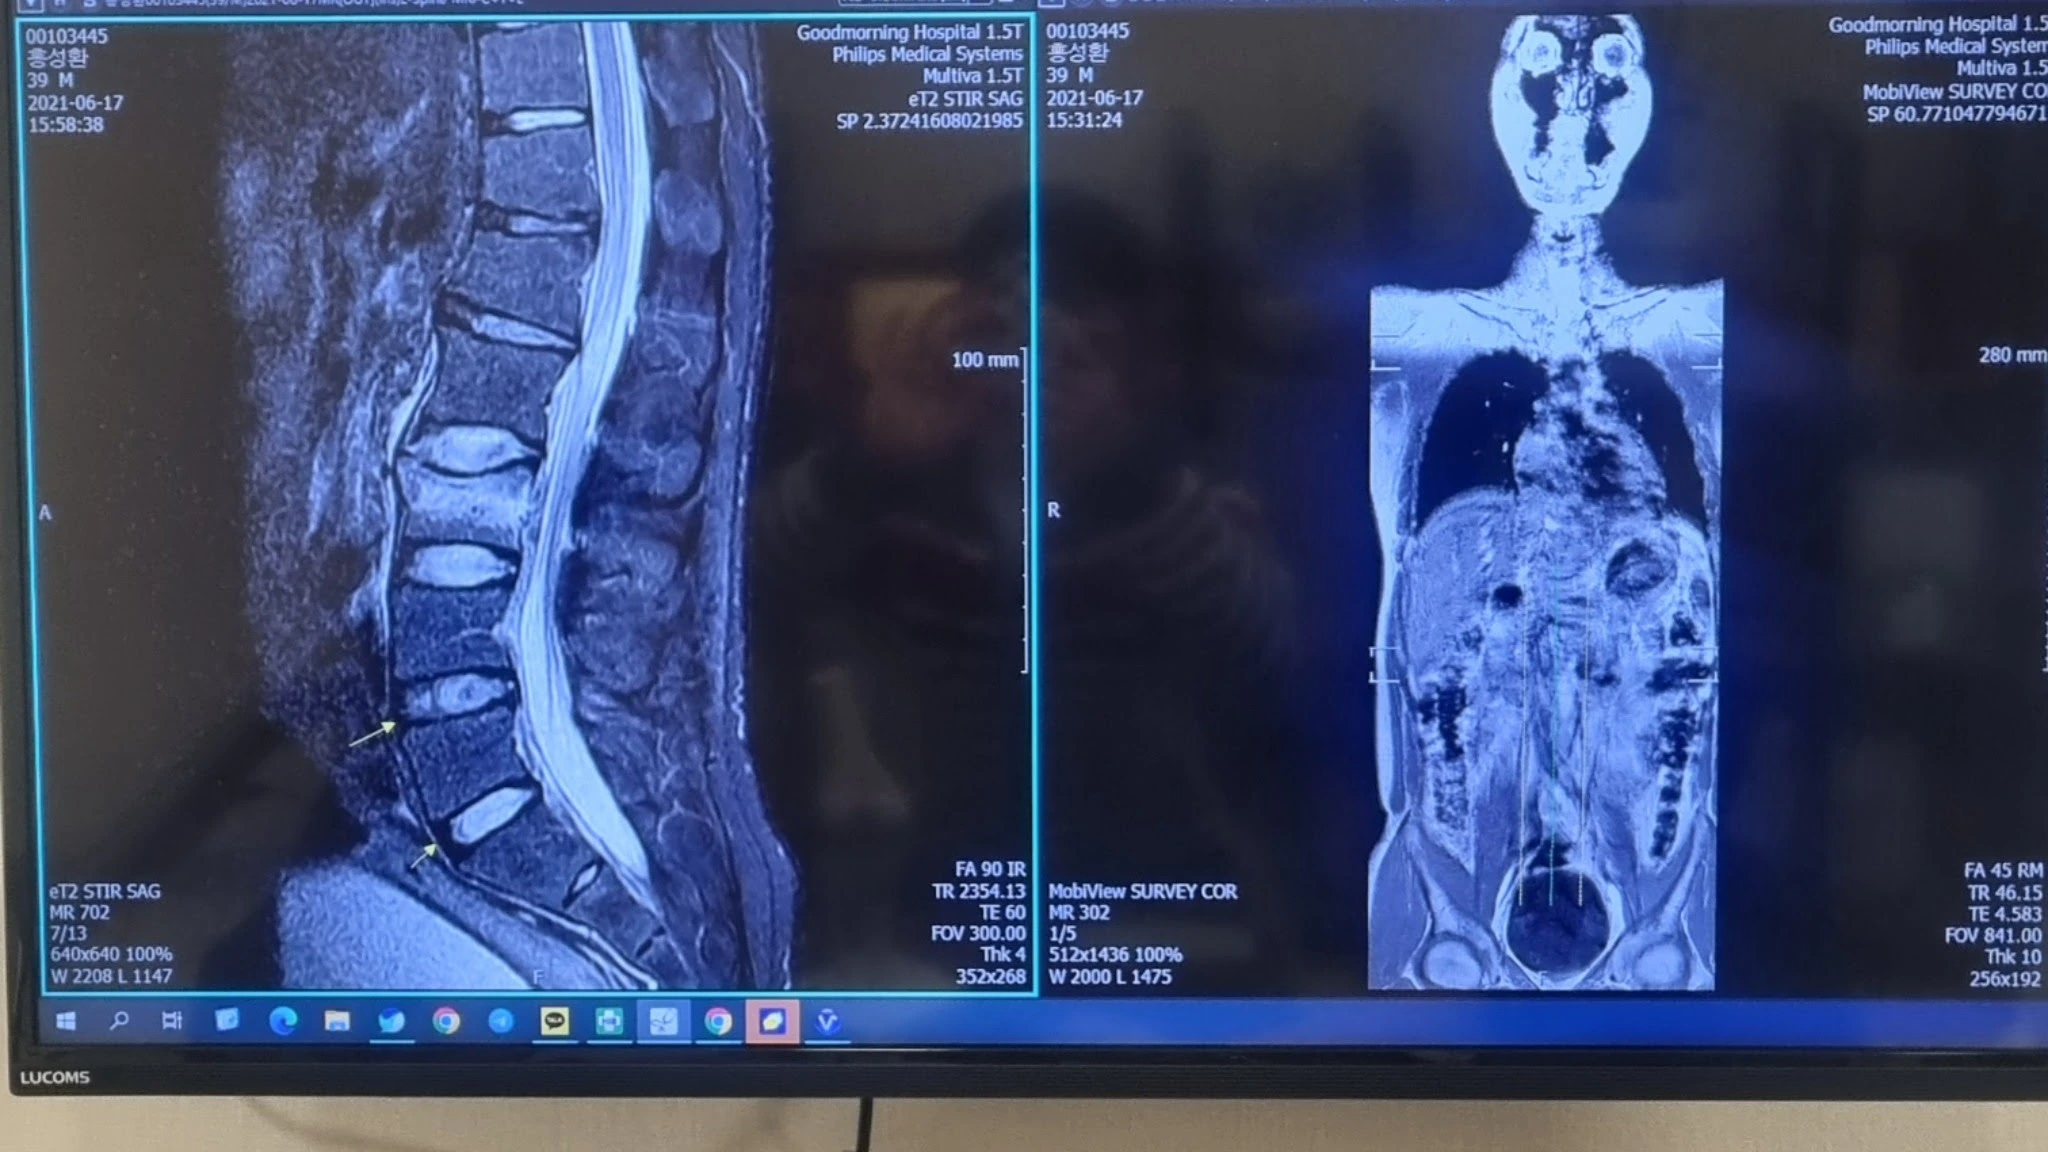

2년전 사고로 왼발 종골 분쇄골절 허리경추2~3번 요추2~3번 압박골절 어깨인대손상 지금은 암 극복중입니다 앞으로 건강을 목적으로 운동하는 채널입니다